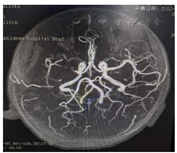

术前头颅MRA报告:1.右侧额颞顶岛叶、右侧基底节区片状异常信号,考虑缺血梗死灶;2.右侧大脑中动脉纤细,分支减少,SWI右侧大脑中动脉M1段呈条状低信号,考虑右侧大。脑中脉栓塞?见图2。